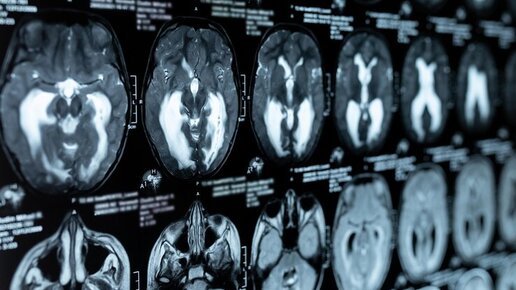

Гидроцефалия – это скопление жидкости в желудочках головного мозга. Избыток спинномозговой жидкости увеличивает размер желудочков и, поскольку череп не гибкий, оказывает давление на мозг. Желудочковая система головного мозга состоит из четырех камер, содержащих большую часть спинномозговой жидкости. Две верхние камеры, называемые левым боковым желудочком и правым боковым желудочком, соединяются с третьей камерой, которая впадает в четвертую камеру, затем на поверхность головного мозга и вокруг спинного мозга...

Головной и спинной мозг окружены специфической по составу и свойствам жидкостью, которую называют спинномозговой (цереброспинальной) жидкостью или ликвором. Свежая спинномозговая жидкость непрерывно производится мозгом каждый день. Он циркулирует вокруг головного и спинного мозга, перенося питательные вещества, смывая загрязнения, отводя продукты метаболизма и смягчая сотрясения, удары в области этих деликатных структур. Спинномозговая жидкость течет через систему желудочков внутри головного мозга,...